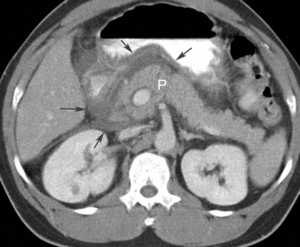

Что такое КТ и когда его назначают

КТ, или компьютерная томография – это один из диагностических способов визуализации работоспособности паренхиматозных органов.

Показания, по наличию которых назначается компьютерная диагностика:

- развитие аномальных процессов в области паренхиматозных органов,

- появление опухолевидных новообразований с различной этиологией,

- при формировании камней в панкреатических протоках ,

- посттравматическое состояние,

- острый панкреатит,

- хронический панкреатит,

- обследование забрюшинной области.

Кроме всего прочего КТ диагностика может назначаться перед проведением хирургического вмешательства. А также огромное значение имеет КТ при раке поджелудочной железы, так как дает большую информативность по расположению региональных метастаз в области близлежащих органов и тканей.